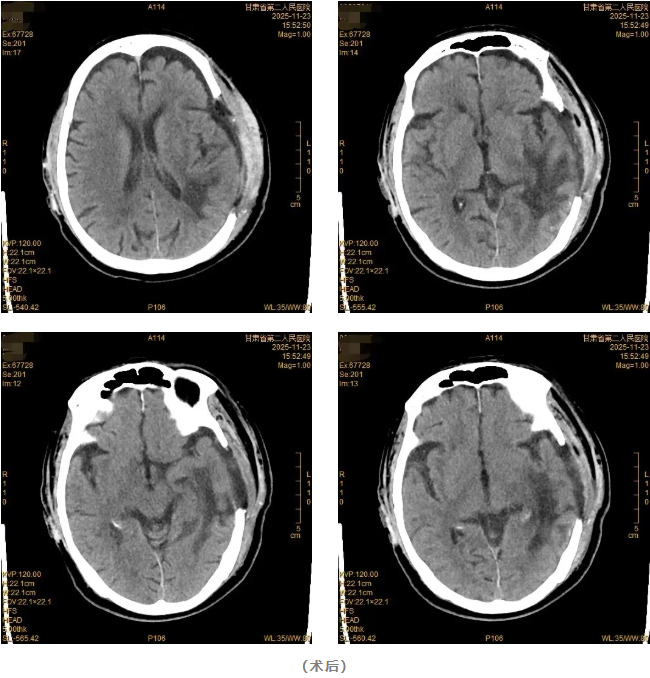

该患者因“突发意识不清伴右侧肢体无力9小时”由120急救车送至成人导航 。急诊查头颅CT显示:左侧颞顶叶脑出血,出血量约70ml。神经疾病中心团队迅速完善术前准备后,急诊为患者施行开颅血肿清除手术。手术过程顺利,术后患者意识逐渐恢复清醒,复查头颅CT确认颅内血肿已清除。

术后早期,患者在重症监护室(ICU)接受严密监护与治疗,生命体征平稳后转入普通病房继续康复。在神经疾病中心医护团队的精心治疗与康复指导下,患者肢体力量逐步好转,能够在辅助下下地行走,恢复进展良好。